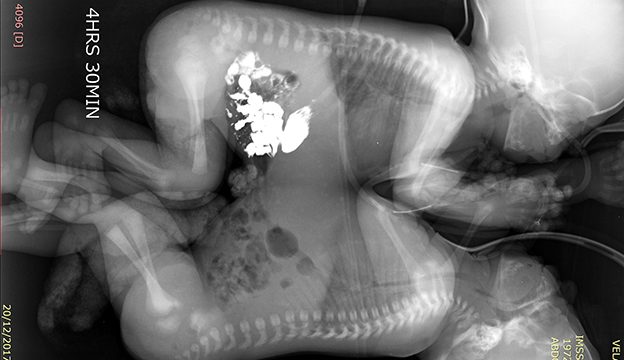

Tras diversos exámenes de tomografía, ecocardiograma y resonancia magnética, cuando los niños cumplieron 41 días de vida, fueron programados para la cirugía que los separaría.